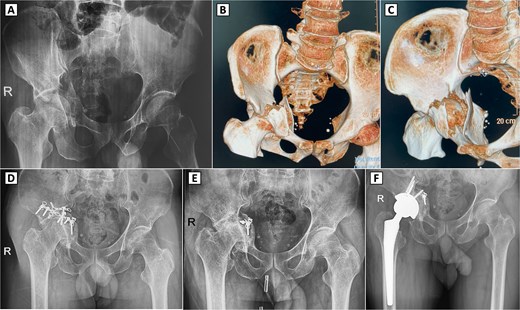

A 49-year-old male sustained a complex right acetabular fracture from a motor vehicle accident and was treated with ORIF via an anterior approach (Fig. 2A–C). The patient resumed ambulation with occasional hip pain and did not require analgesics. Seven months post-ORIF, worsening activity-related pain and a limping gait emerged, with restricted ROM (83° flexion, 7° extension, 29° internal rotation, 38° external rotation, 30° abduction, and 10° adduction). Radiographs showed partial hardware loosening, posterior femoral head displacement, joint space narrowing, femoral head deformity, and secondary osteoarthritis (Kellgren-Lawrence grade II) despite bone union (Fig. 2D). Hardware removal revealed a fractured reconstruction plate, with most components removed, except for a deeply positioned fragment deemed non-interfering for THA (Fig. 2E). Four months later, radiographs confirmed screw hole healing but progression to Kellgren-Lawrence grade IV osteoarthritis. THA via a direct lateral approach required bone grafting due to acetabular bone loss, using autogenous bone from acetabular reaming and the femoral head (Fig. 2F). Two years post-THA, hip function improved significantly without complications.

Preoperative imaging, 3D CT reconstruction, and postoperative radiographs with complex right acetabular fracture and subsequent surgical interventions. (A) Preoperative anteroposterior (AP) pelvic X-ray demonstrating a displaced right acetabular fracture with protrusion of the femoral head into the pelvis. (B, C) 3D computed tomography (CT) reconstructions (anterior and superior views, respectively) revealing the comminuted acetabular fracture involving the posterior column and posterior wall. (D) Postoperative AP pelvic radiograph showing internal fixation of the right acetabulum with reconstruction plates and screws. (E) Radiograph after hardware removal, with partial retention of fixation material, demonstrating secondary osteoarthritis of the right hip joint, including joint space narrowing and femoral head deformity. (F) Postoperative X-ray following the conversion total hip arthroplasty.